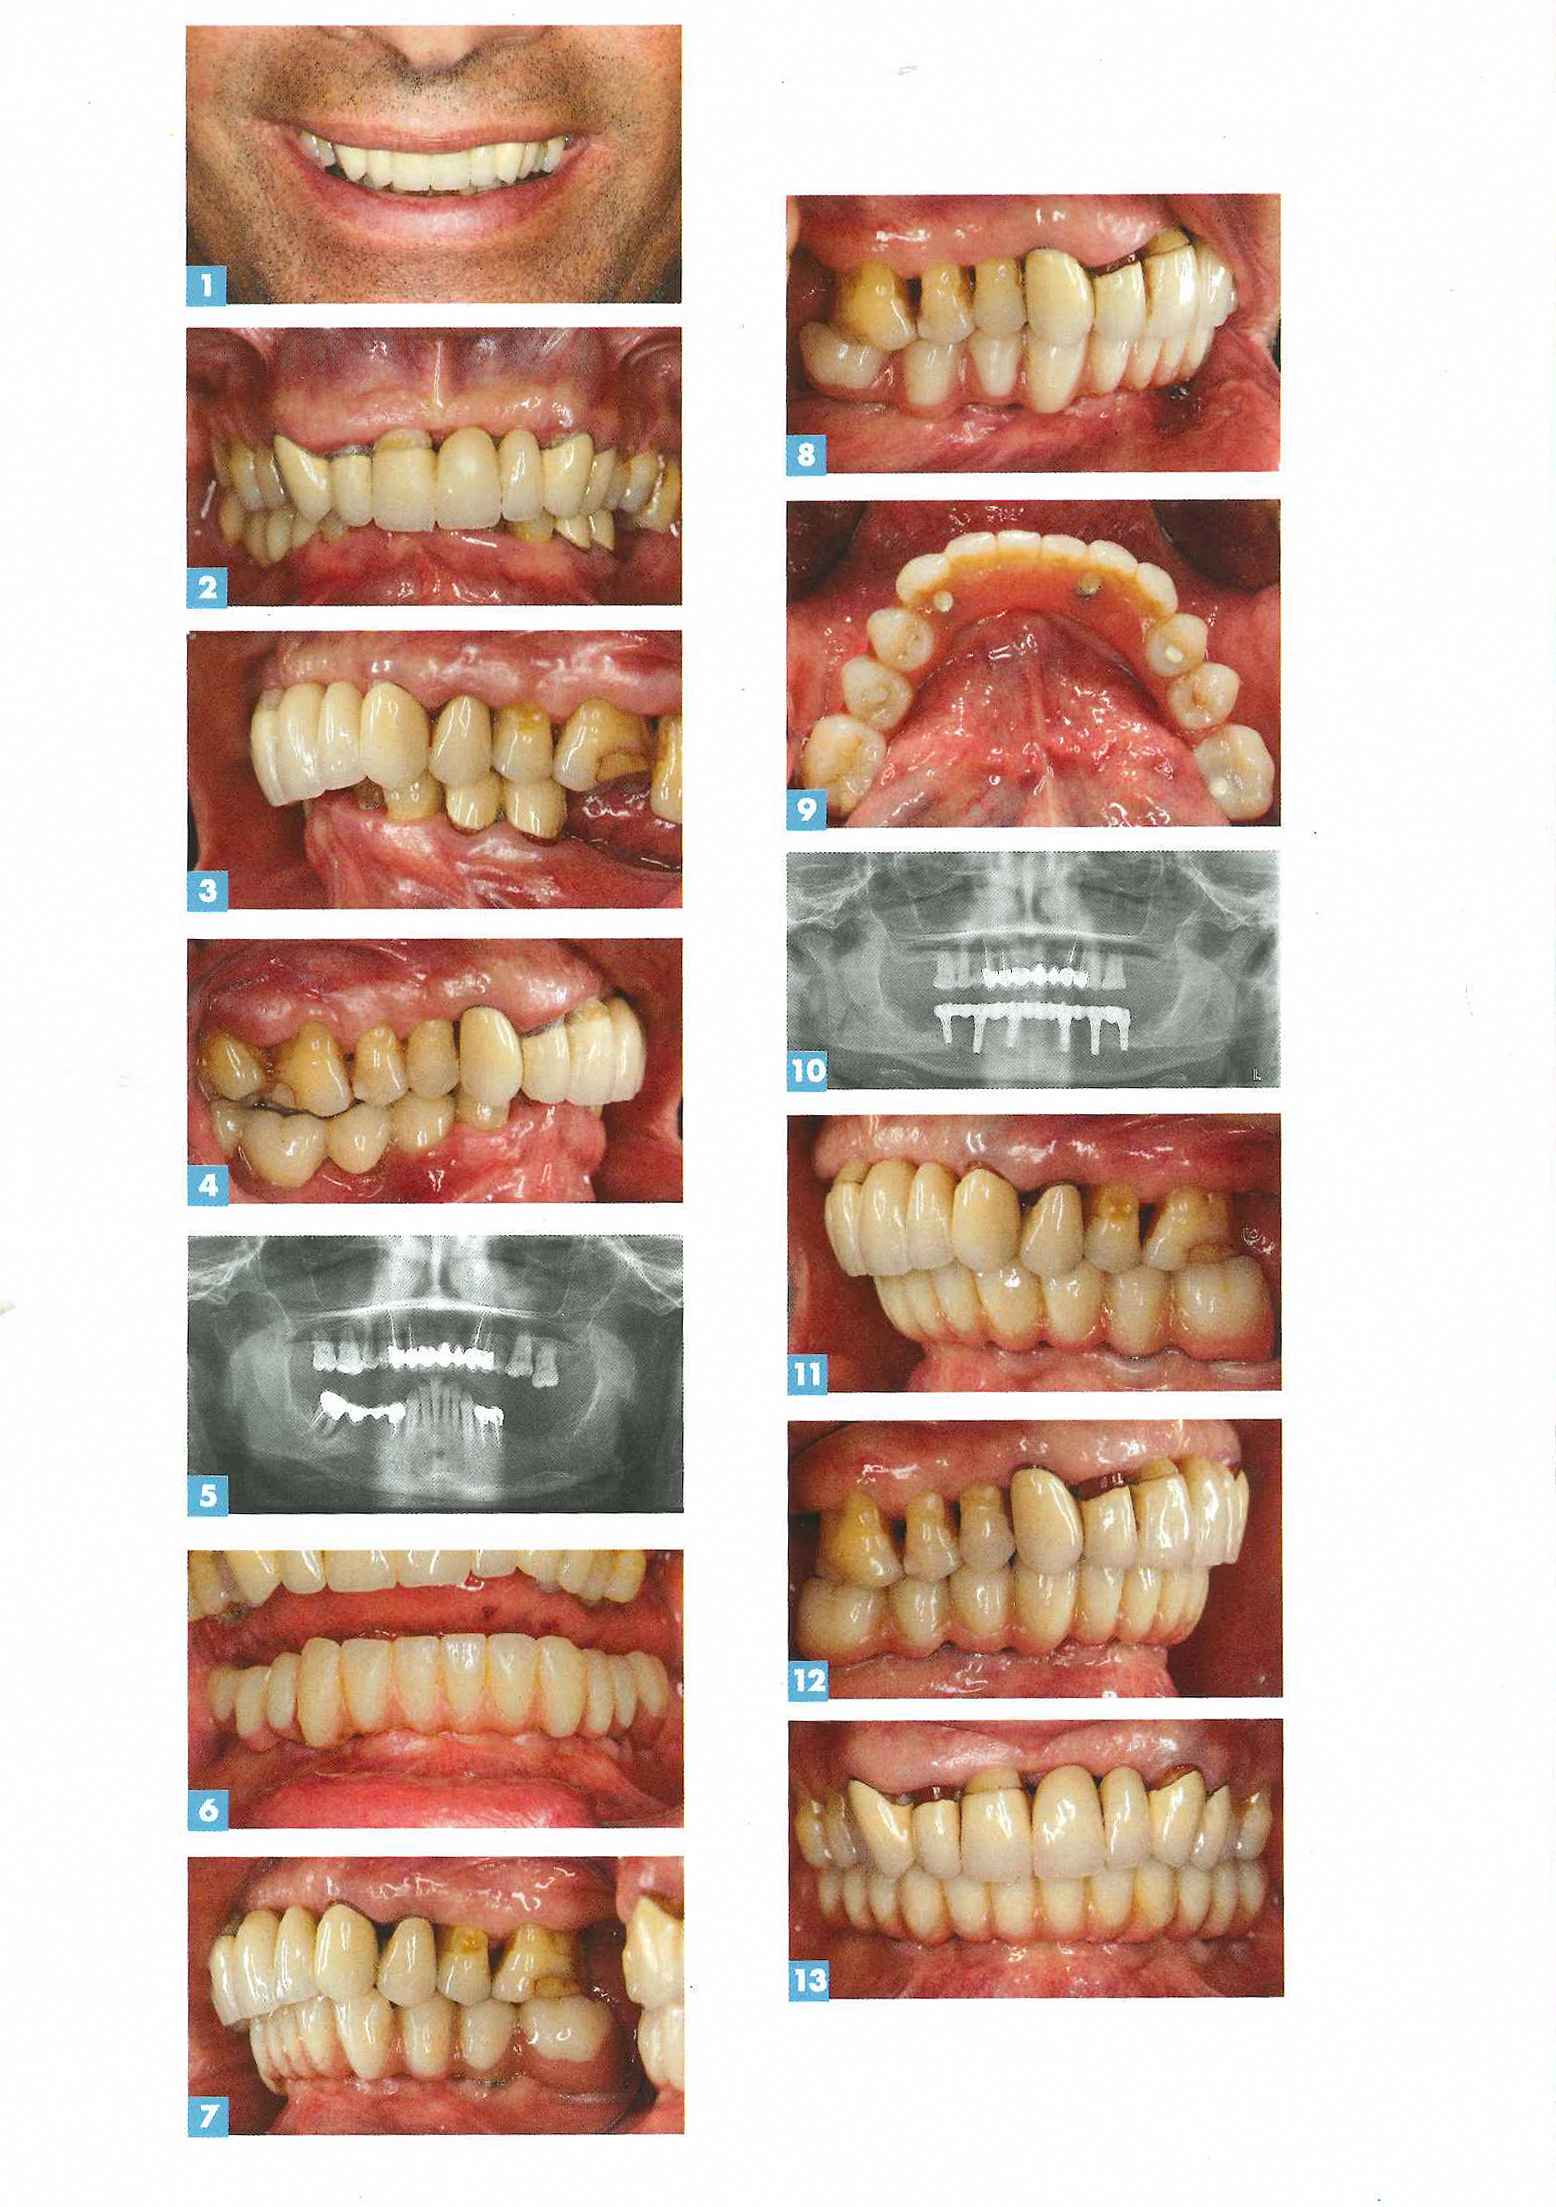

Réhabilitation prothétique complète du maxillaire atrophié